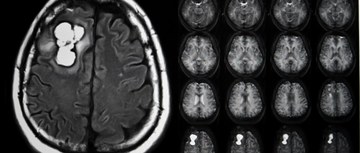

X-ray of brain with desmoid tumors

Drug Updates Tools and Resources

Pharmacist’s Application to Practice: Nirogacestat (Ogsiveo)

Brooke Lochridge, PharmD ,PGY-2 Oncology Pharmacy Resident, of Tristar Centennial Medical Center, Nashville, TN, and Colleen McCabe, PharmD, BCOP, Oncology Clinical Specialist, Sarcoma & Melanoma from Vanderbilt University Medical Center, Nashville, TN w